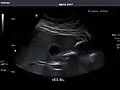

Right kidney

Kidneys: Right and left kidneys measure 11.5 cm and 12 cm in length respectively. No hydronephrosis. Small left lower pole kidney cyst.